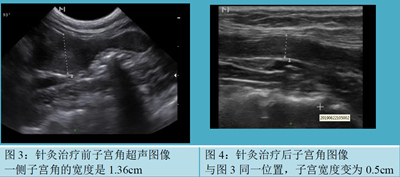

检查: 该猫精神状态一般, 4/9 BSC,该猫对人很友好,但对外界环境警惕性很高。 血常规检查WBC升高,腹部超声检查发现子宫扩张,一侧子宫角的宽度是1.36cm (见图3),这个子宫角比正常的变宽而且子宫壁也比正常的变厚,该体型的猫正常的子宫角宽度在0.5cm左右。 从西医的角度考虑子宫内膜炎甚至子宫蓄脓初期,建议手术切除,但是介于该猫子宫增大,手术切口可能需要切3cm左右,主人希望能做微创切口(1cm以内)的切口,这样计划先将子宫恢复成正常大小后再进行手术。 跟主人沟通后尝试用针灸进行治疗。

针灸和中药治疗效果: 该猫2019年6月19号就诊,进行第1次针灸治疗,针灸后该猫阴部的脓血减少了90%(见图2); 然后隔天做一次针灸,2次针灸后超声监控子宫恢复到正常图像(见图4),子宫的宽度只有0.5cm. 随后该猫又继续做了2次针灸巩固疗效。2019年8月5日子宫超声监控一切正常,根据主人意愿做了微创手术绝育,切口不到1cm,切除的子宫没有明显肉眼可见异常。